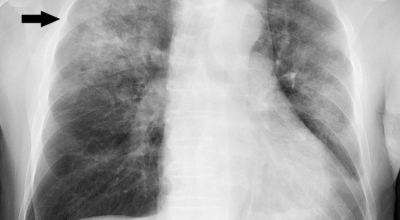

증상을 겪는 경우 배양 검사는 물론 X-ray 촬영 등을 통해 진단을 할 수 있어요. 필요한 경우 소변, 혈액, 혈청 검사, CT 등이 추가적으로 진행돼요.

진단을 받은 환자에게서 입원이 권고되지는 않으나 나이가 어린 경우 혹은 반대로 기저 질환이 있거나 호흡곤란이 심한 상태, 나이가 많은 경우에는 임산부 과 같은 경우, 빠른 치료와 상태의 호전, 위험성에 대한 관리를 위해 입원치료를 진행합니다. 폐렴 치료에 있어 가장 중요한 것은 항생제 치료로 원인균에 해당하는 항생제를 처방하게 되는데 이는 세균, 바이러스 감염에 의한 발생인 경우에 해당하며 초기에는 항바이러스제를 통해 감기처럼 치료를 시도하기도 합니다.